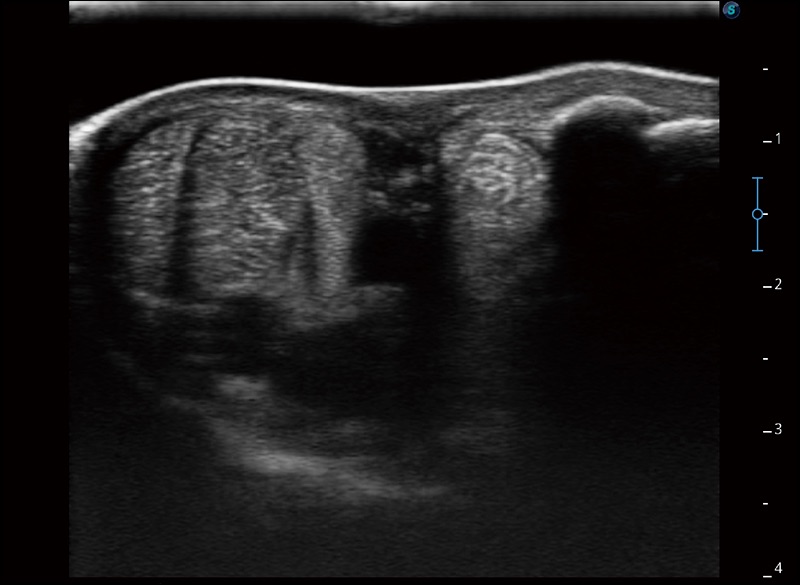

连续波多普勒成像CW

为心脏功能评估提供更多诊断信息